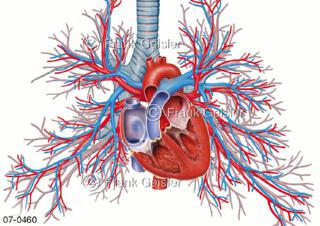

Bildergalerie Herz, Blutkreislauf

Bilder zu Herz, ein muskuläres Hohlorgan, das den menschlichen Körper durch rhythmische Kontraktionen mit Blut versorgt und dadurch die Durchblutung der Organe sichert, das Kreislaufsystem zeigt den Transport von arteriellem sowie venösem Blut durch das kardiovaskuläre System (Herz-Kreislauf-System), bestehend aus Blutgefäßen, Lymphgefäßen und dem Herz